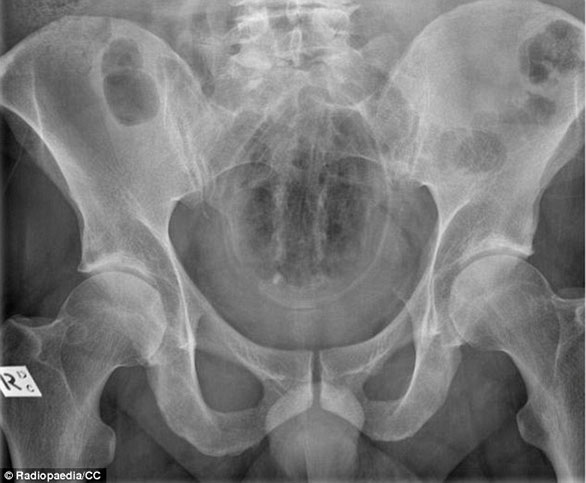

ضم الموقع مجموعة من الصور للأشعة السينية توضح أجساماً غريبة رُصدت داخل أجساد المرضى، ما أثارت دهشة الأطباء الذين قرروا رفعها على موقع طبي متخصص كمادة تعليمية ومرجعية بحثية واستشارية للدارسين في كليات الطب، والذي أنشئ من قبل طبيب أشعة أسترالي عام 2005، بحسب صحيفة دايلي ميل البريطانية.

صورة لأشعة "إكس راي" تُبين دخول باذنجان.

صورة لأشعة "إكس راي" توضح ابتلاع برتقالة كاملة بقشرها.